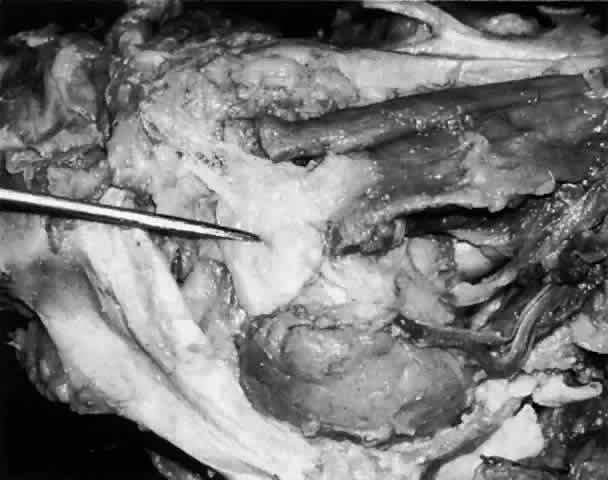

The main lacrimal gland resides in the superotemporal orbit, partially within a shallow bony fossa in the lateral angular process of the frontal bone (fossa glandula lacrimalis). The gland is situated between the eyeball below and the curved orbital wall above, giving it a somewhat compressed and curved shape. It may extend inferiorly to the lateral canthal tendon. The lateral horn of the levator aponeurosis crosses the gland anteriorly, separating it into a larger superior or orbital lobe and a smaller inferior or palpebral lobe (Fig. 2). The division is incomplete because the larger orbital lobe is connected to the smaller palpebral lobe posteriorly by a bridge of glandular tissue, draining tubules, and Müller's muscle, which is attached to the underside of the levator muscle and aponeurosis. The lacrimal gland is surrounded by fibrous tissue that is attached superiorly to the periosteum of the frontal bone and inferiorly to the orbital portion of the zygomatic bone.1

Fig. 2. With the roof and lateral wall of the left orbit removed, this cadaver dissection demonstrates the orbital lobe (black arrow) and the palpebral lobe (white arrow) separated by the lateral horn of the levator aponeurosis (pointer).